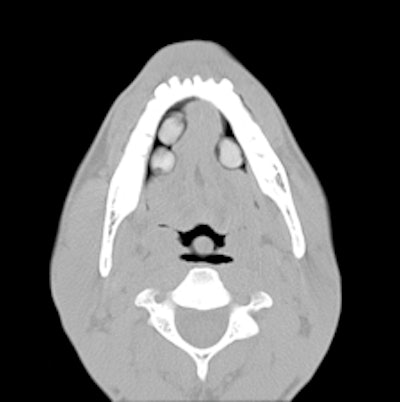

Top left: Axial plane in pulmonary window showing three pellets underneath the tongue. Top right: 3D reconstruction of an incidental finding of three sublingual cocaine pellets in a case of brawl/fist fight with subsequent CT and scan of the viscerocranium. The patient was immediately put under arrest and transferred to the affiliated custody ward. This scan was performed to rule out facial fractures sustained during the fist fight. Bottom left: Secured evidence of similar pellets (weight approximately 1 g). Bottom right: 3D reconstruction of gas-filled condom with two pouches (bags) of cocaine powder inside located in the descending colon. All images courtesy of Dr. Patricia Flach.To determine which diagnostic imaging procedures produce the best results, radiologists from Bern and Zurich compared the accuracy of different modalities in a retrospective study. They evaluated 35 CT exams, 70 digital radiography (DR) exams, and 30 low-dose linear slit digital radiography (LSDR, Lodox Systems) exams taken of 83 suspects between February 2004 and April 2011.